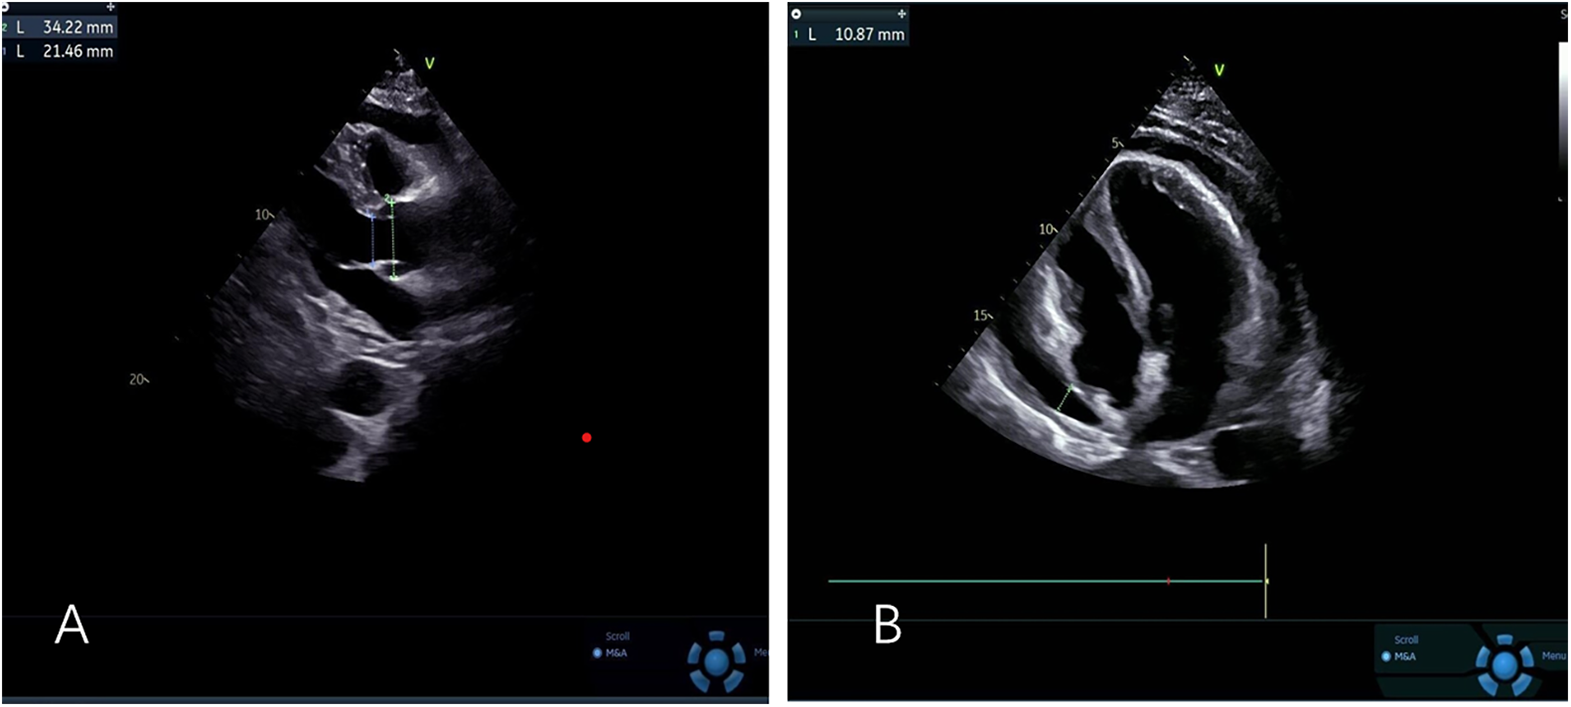

The patient's initial echocardiogram showed only minimal pericardial effusion (Figure 1A), managed expectantly. Upon admission, ultrasound revealed worsening effusion (14 mm RV anterior wall) with fibrinous strands (Figure 1B). Combined with the patient's signs of low-grade fever, pericardial friction rub and laboratory findings (white blood cell count 14.4 × 10⁹/L, neutrophil proportion 85.0%, CRP 140.9 mg/L), infectious inflammation was highly suspected clinically. Given the rapid progression of the patient's condition, to avoid delaying anti-infective treatment, blood culture or pericardial fluid culture was not performed, and an empirical anti-inflammatory regimen was initiated: anti-inflammatory treatment was administered with Cefoperazone Sodium and Tazobactam Sodium for Injection combined with 40 mg of intravenous methylprednisolone in 100 mL of normal saline. The pivotal diagnostic moment came on day 5 when echocardiography detected rotating microbubbles near the AV groove, suggesting fistulous gas entry—later confirmed by CT as pneumopericardium (Figure 2; Supplementary Movies 1–2).

Figure 1

(A) Left ventricular long-axis view reveals minimal pericardial effusion (B) apical four-chamber view demonstrates mild to moderate pericardial effusion.